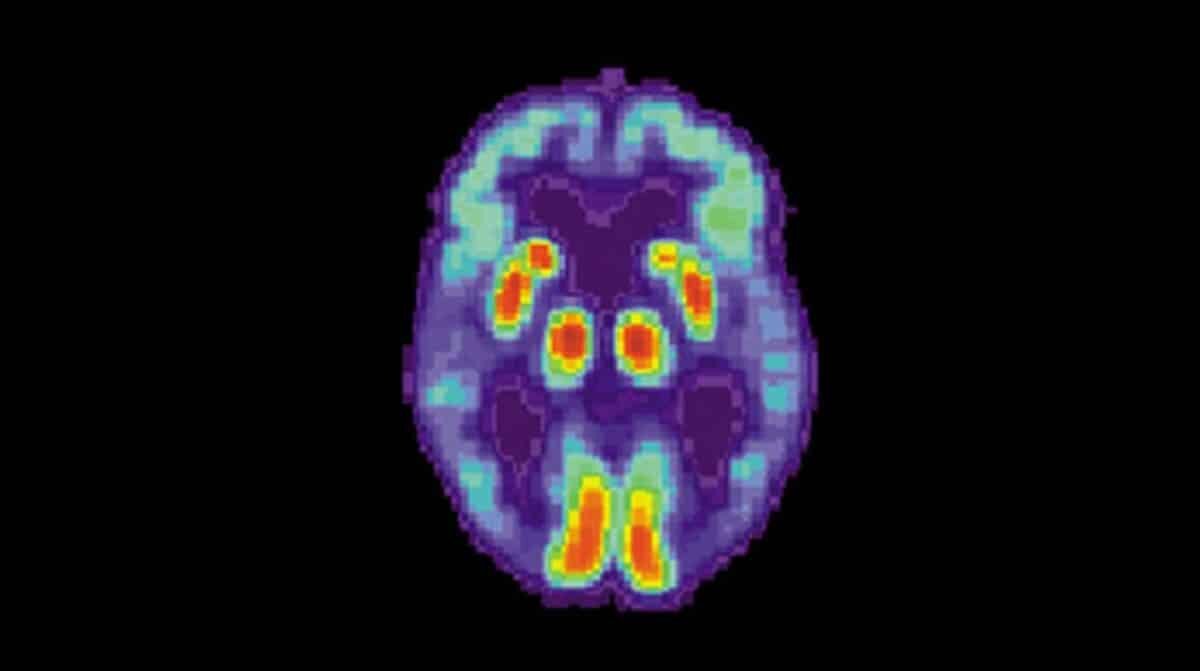

ПЭТ-сканирование мозга пациента с болезнью Альцгеймера. / National Institute on Aging